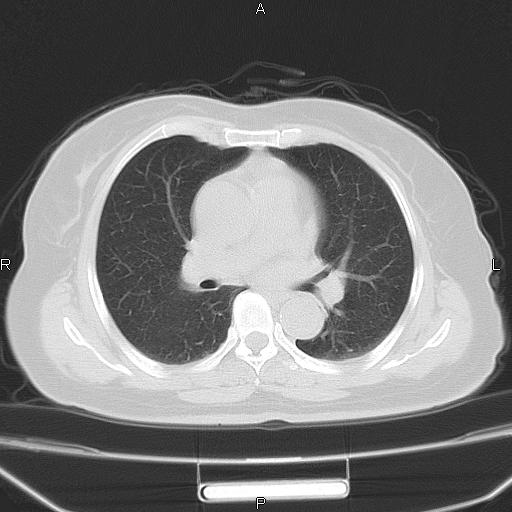

胸腺瘤

女、63Y 双眼睑下垂,早轻晚重。 胸腺瘤???

结果胸腺瘤